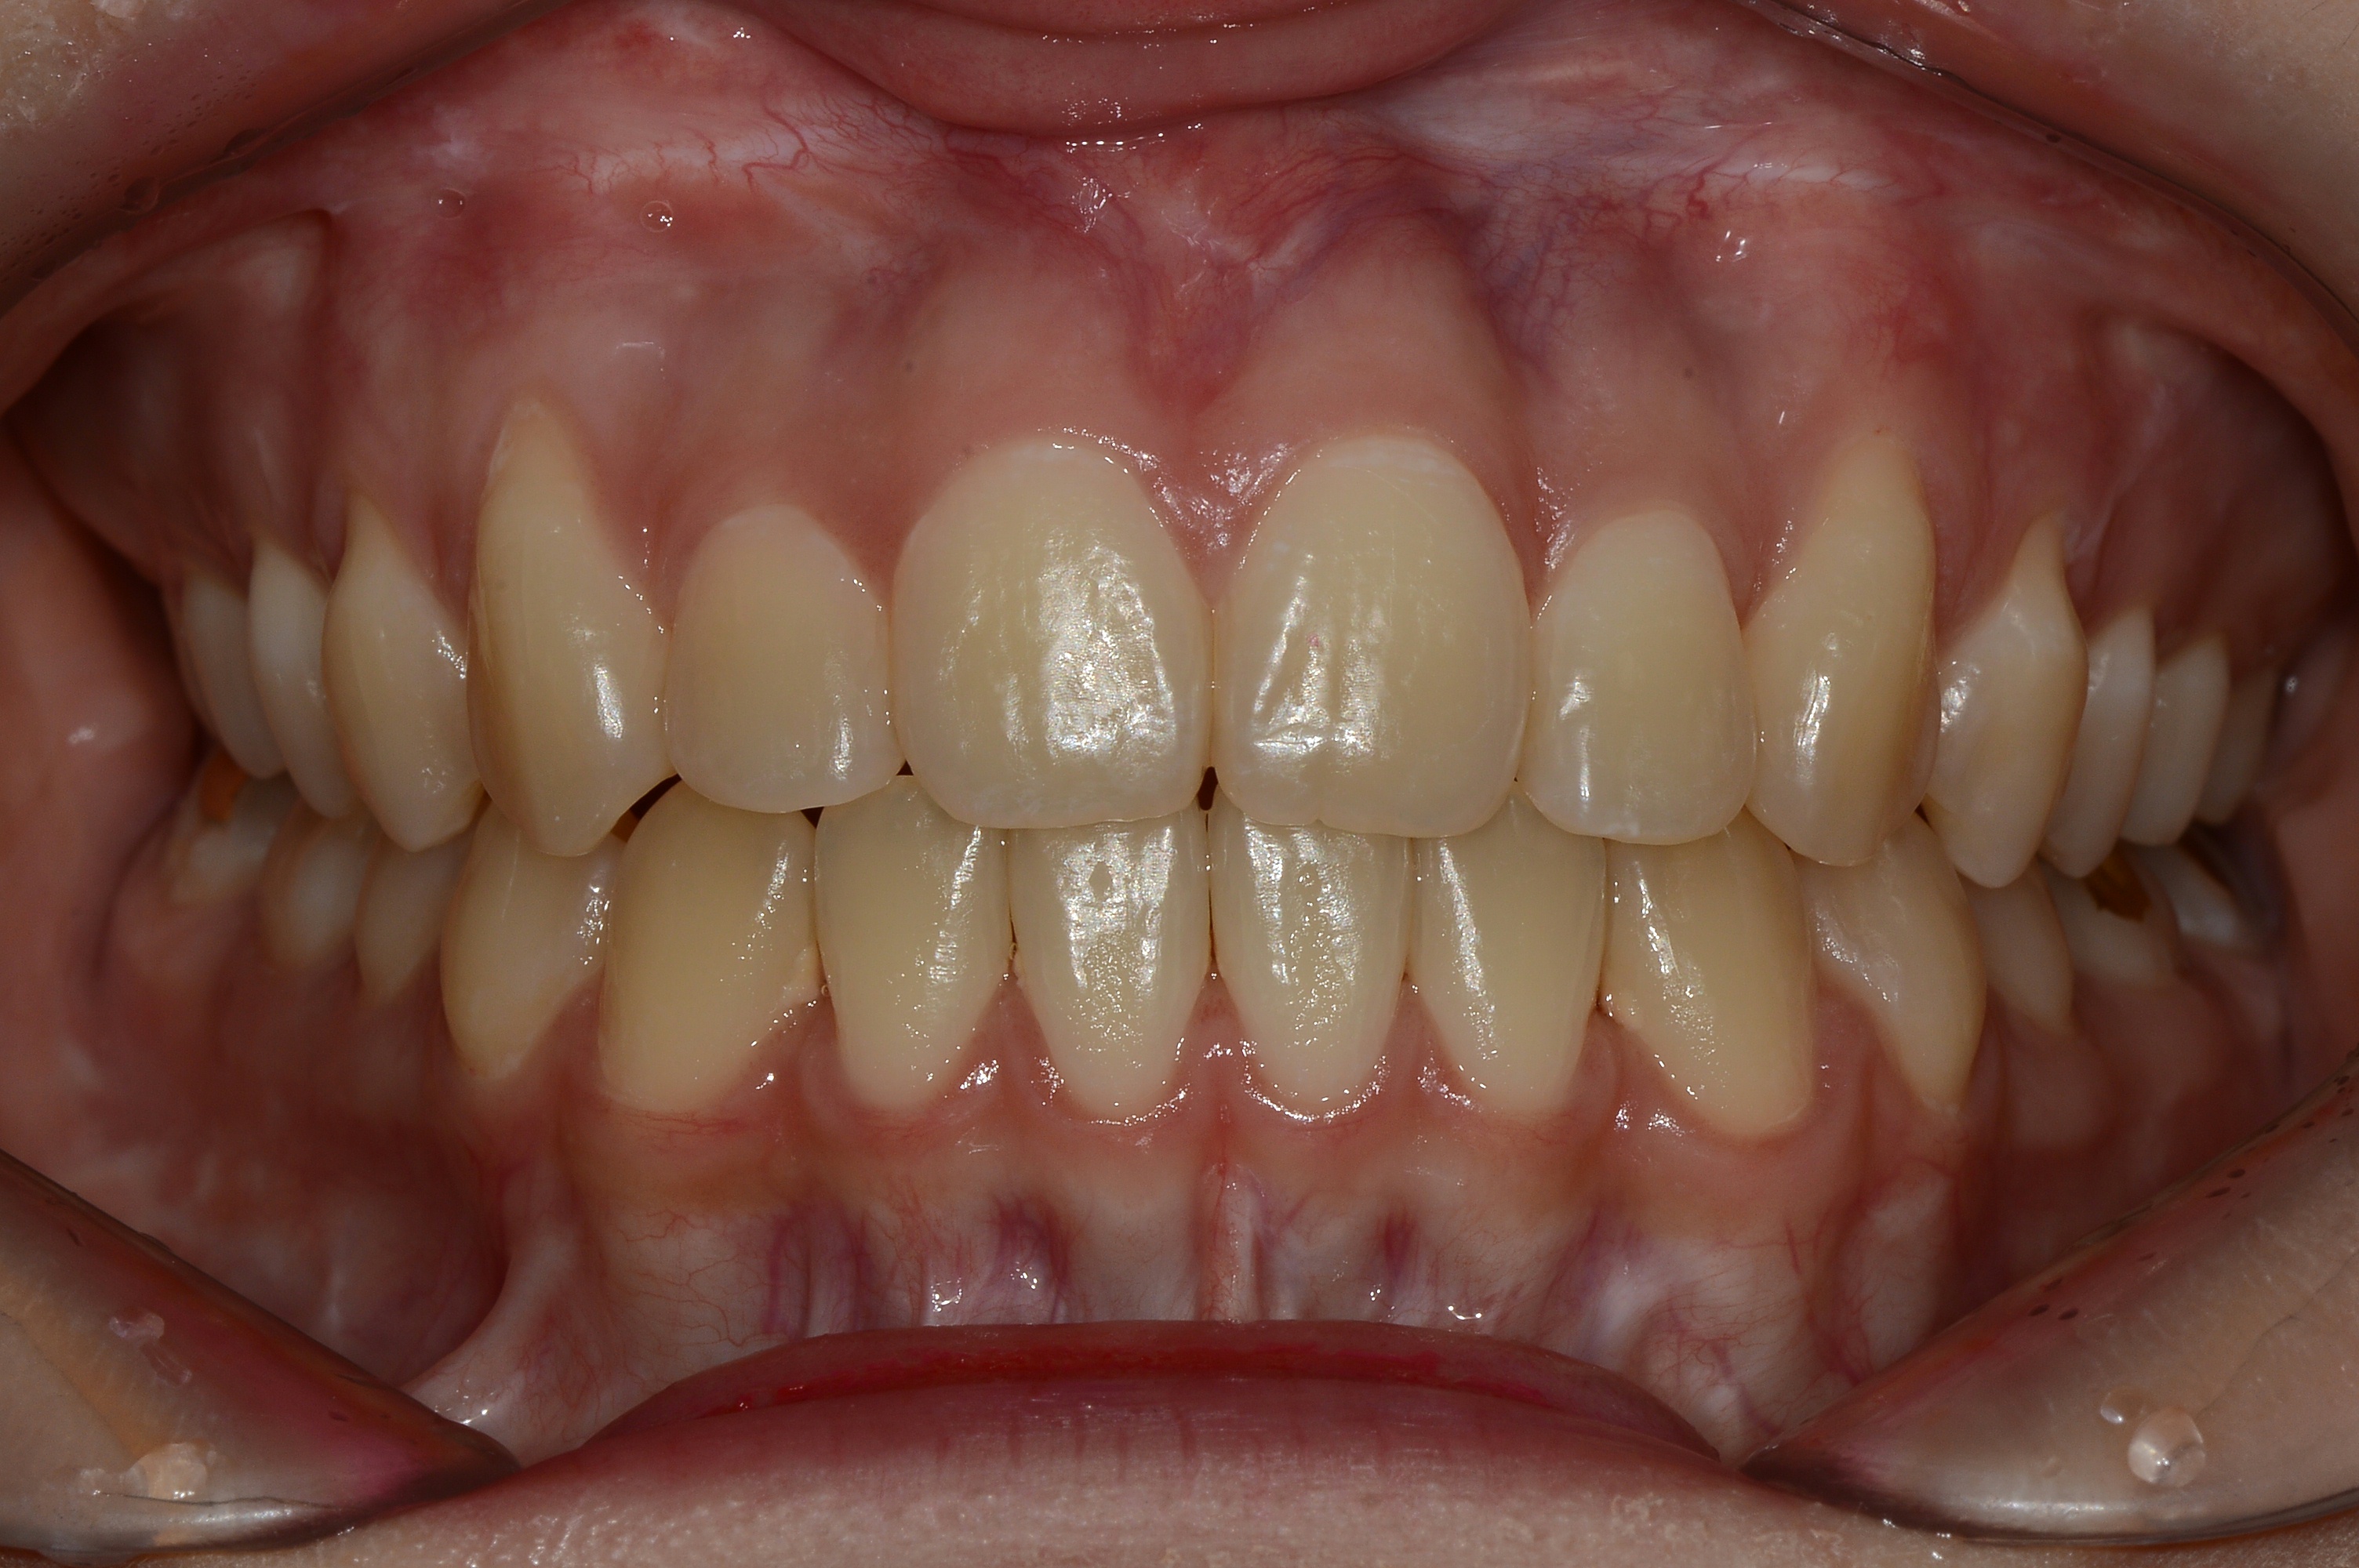

치료 후 사진입니다.